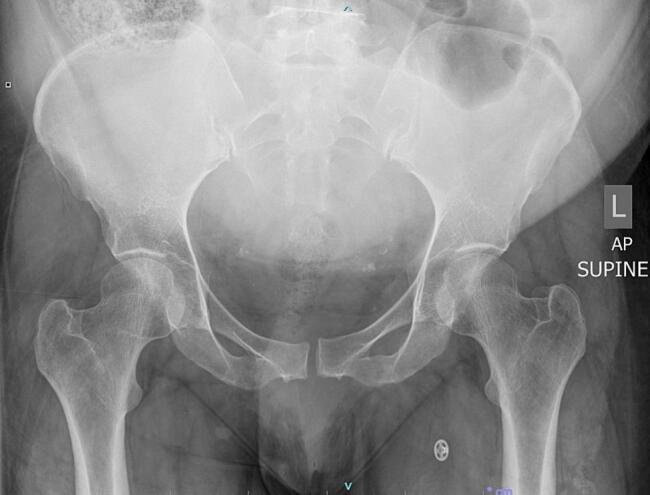

MRSA septic arthritis of the pubic symphysis post vaginal delivery: A case report and literature review.

We report the case of a 36-year-old woman who developed septic arthritis of the pubic symphysis caused by MRSA after spontaneous vaginal delivery.

Differentiating between diastasis and septic arthritis of the pubic symphysis is crucial for treatment. Noninfective pubic osteitis can mimic septic arthritis, presenting a diagnostic challenge. Imaging, laboratory data, and cultures are essential for accurate diagnosis. MRSA colonisation during pregnancy and postpartum trauma may facilitate infection. MRI is the most sensitive imaging modality for early detection and monitoring.